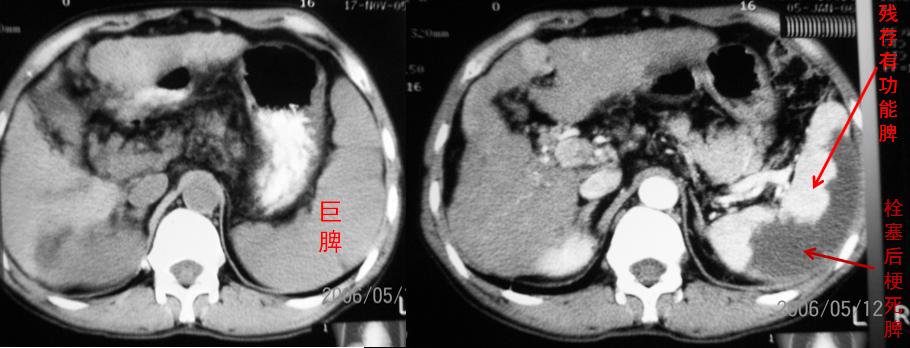

巨脾栓塞前后CT对照,右图栓塞后部分脾梗死而失去功能

所谓部分性栓塞,是指只栓塞显得多余的那部分(通常是60~80%),而用来维持正常功能的那部分则需要留下。

值得注意的是,部分患者的脾脏实在太大,可采取分次栓塞的办法,防止过于强烈的栓塞后反应。尽管PSE是微创操作,术前术后当然也需要关注一些细节,不过,那是医护人员的事,普通公众只需做到遵医嘱就可以了。